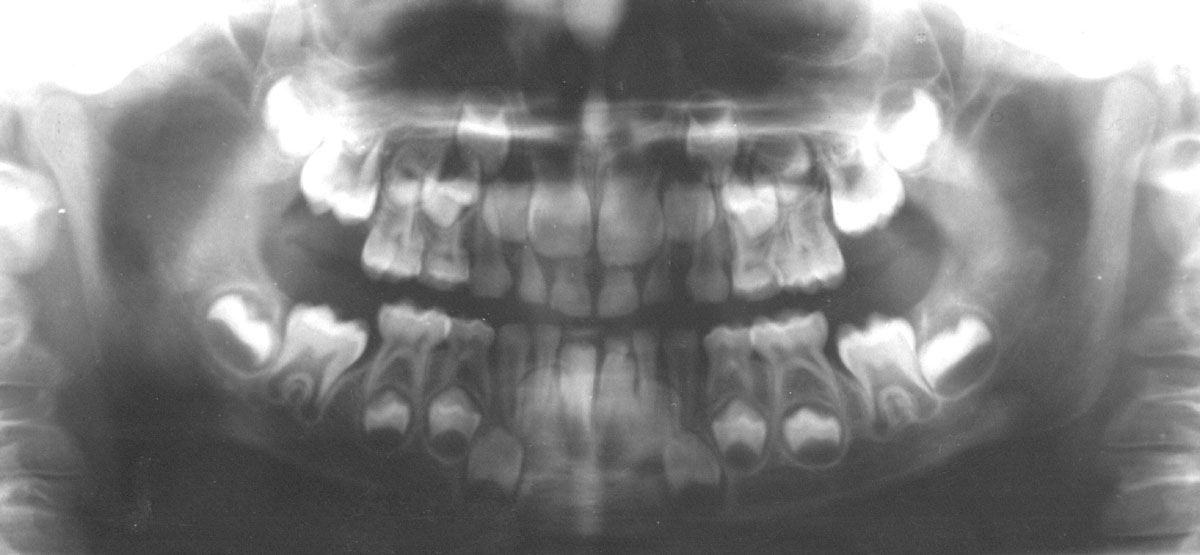

A panoramic radiograph is a panoramic scanning dental X-ray of the upper and lower jaw. It shows a two-dimensional view of a half-circle from ear to ear.

The X-rays use small amounts of radiation. Panoramic X-rays show a broad view of the jaws, teeth, sinuses, nasal area, and temporomandibular (jaw) joints. These X-rays show problems such as impacted teeth, bone abnormalities, cysts, solid growths (tumors), infections, and fractures